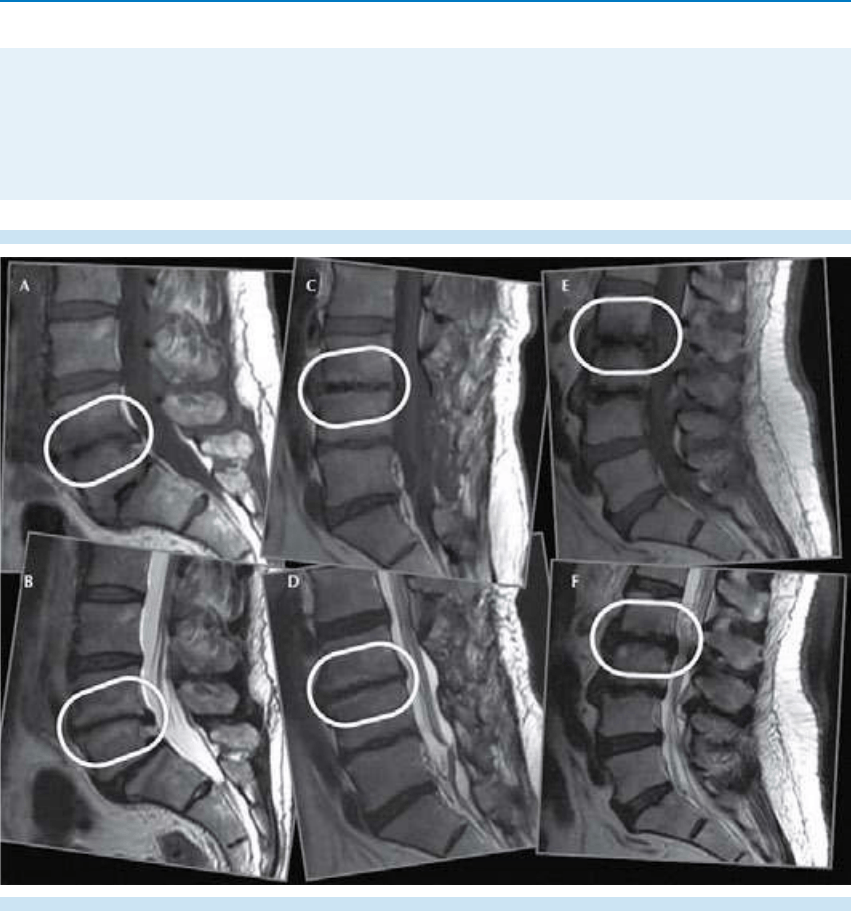

2. Morfología y alineación de los cuerpos

vertebrales, evaluación de los ligamentos.

3. Evaluación del disco intervertebral.